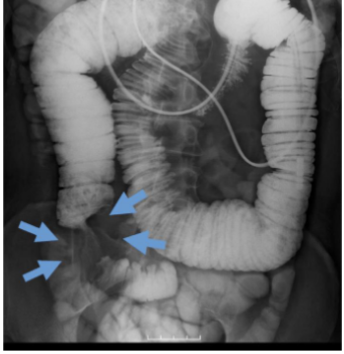

Diverticulosis, Barium Enema

What is this and what type of scan